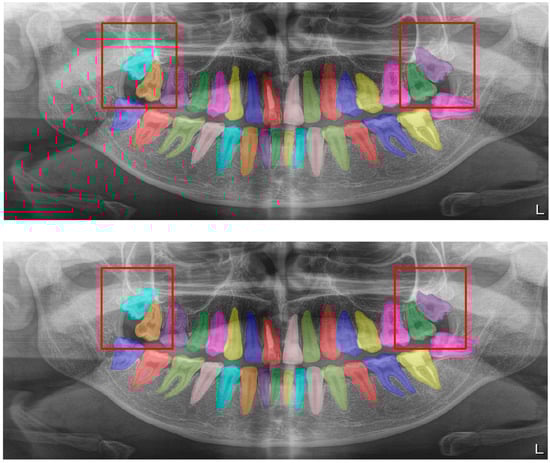

Figure 8.

Erroneous automatic segmentation at the maxillary left third molar due to the superimposition between the maxillary sinus floor and root apices of the tooth. Manual segmentation (upper image) and automatic segmentation (lower image) can be seen above.

Figure 9.

Erroneous automatic segmentation at the mandibular left second molar due to the superimposition between the mandibular left first and mandibular left second premolars. Manual segmentation (upper image) and automatic segmentation (lower image) can be seen above.

Most of the erroneous segmentations occurred due to the limitations of OPG devices, and some of the examples are as follows:

In Figure 8, a more successful automatic segmentation is observed at the maxillary right third molar than the maxillary left third molar, and a missing segmented area in the form of a notch is observed. As most of the upper third molars were superimposed on the floor of the maxillary sinus and zygomatic process of the maxilla, erroneous segmentations were inevitable. In Figure 9, an erroneous automatic segmentation at the mandibular left second molar due to the superimposition between the mandibular left first and mandibular left second premolars can be seen.